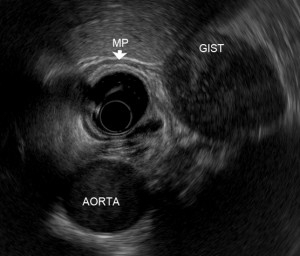

Gastrointestinal stromal tumor (GIST)

Gastrointestinal stromal tumor can be found in any area of the gastrointestinal (GI) track such as esophagus, stomach, pancreases, large intestine, small intestine and appendix. Small GISTs often do not cause symptoms, and are usually discovered incidentally on upper GI endoscopy or computer tomography. Large GISTs may cause abdominal discomfort / pain, or even GI bleeding.